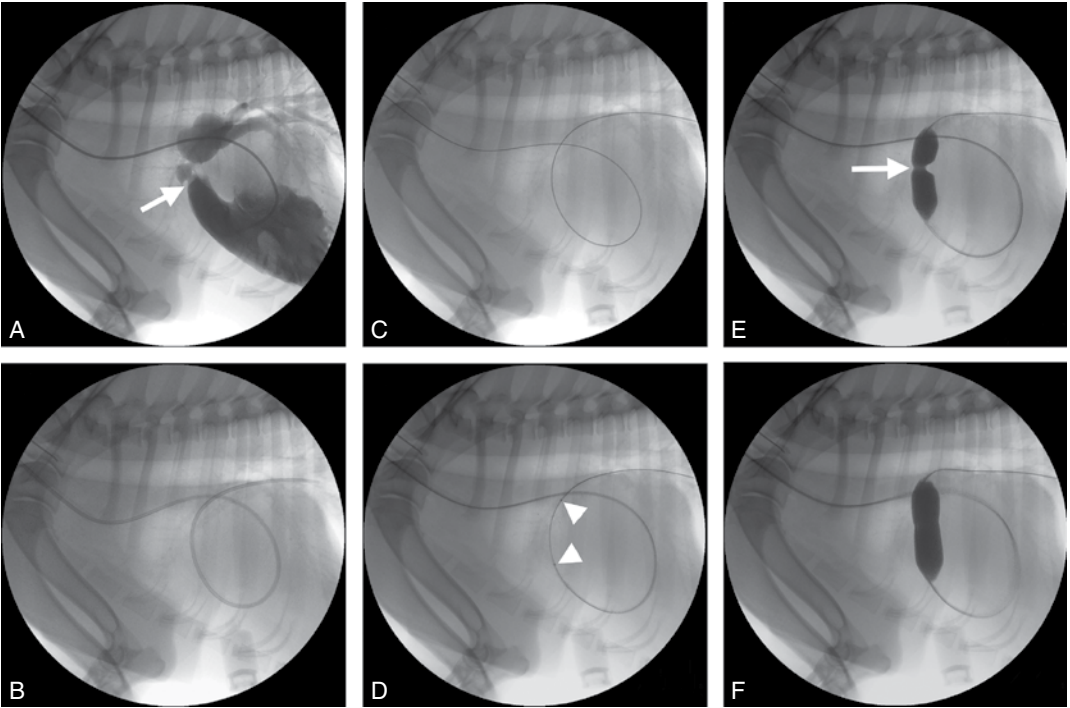

PDA 교정 시술 전후 초음파 비교

시술 전 1

시술 전 2

시술 후 1

시술 후 2

PDA 교정 시술 전후의 초음파 비교입니다. 시술 전에는 동맥관 개존증으로 인한 비정상적인 혈류 패턴이 도플러 초음파로 확인되며, 시술 후에는 PDA plug 삽입으로 정상적인 혈류 패턴으로 회복된 상태를 보여줍니다.